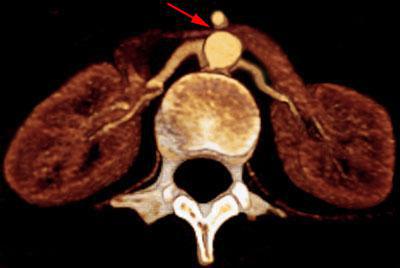

Trombosis de la vena renal izquierda